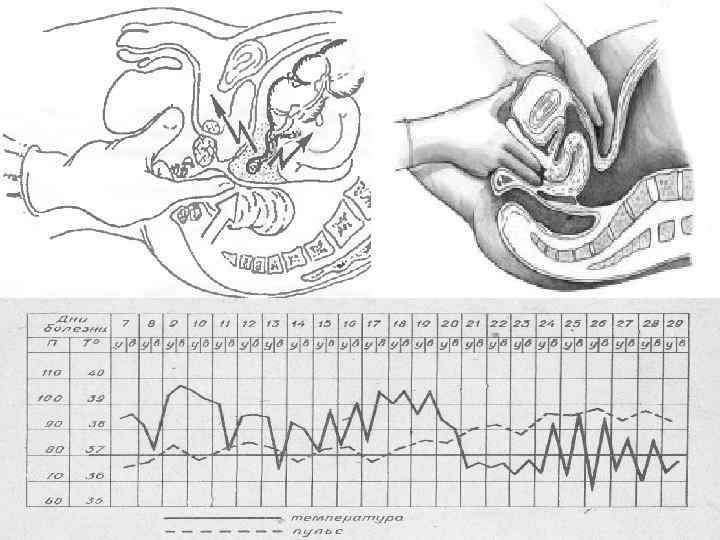

Клиническая картина Основные симптомы: Кохера Волковича – миграция боли из эпигастрия в правую подвздошную область. Раздольского – болезненность при перкуссии в правой подвздошной области. Воскресенского – скольжение правой рукой по натянутой рубашке от эпигастральной области к правой подвздошной с остановкой пальцев в проекции аппендикса. Ровзинга – прижатие в левой подвздошной области толстого кишечника вызывает усиление боли в правой подвздошной области. Образцова – усиление боли при поднятии выпрямленной в колене правой ноги. Ситковского – при перемещении больного на левой бок – усиление боли в правой подвздошной области. Бартомье Михельсона – болезненная пальпация в правой подвздошной области при положении на левом боку. Щеткина Блюмберга – сильная боль при пальпации в правой подвздошной области в момент резкого отнятия руки. Локальная/генерализованная ригидность мышц передней стенки брюшной полости. Симптом болезненности передней стенки прямой кишки – при «пальцевом» ректальном исследовании. Симптом нависания заднего свода влагалища – при влагалищном исследовании. Симптом «Токсических ножниц» учащенный пульс не соответствует температуре(при гангренозной форме).

Кохера-Волковича Воскресенского Щеткина-Блюмберга Ситковского Образцова Ровзинга Бартомье-Михельсона Раздольского